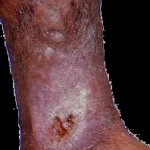

- Στάδιο με επιπλοκές των κιρσών που είναι: αρχικά η σκλήρυνση και υπέρχρωση του δέρματο συνήθως πάνω από τον αστράγαλο και αν ο ασθενής μείνει χωρίς θεραπεία η δημιουργία ενό( έλκους που δεν θεραπεύεται εύκολα (άτονο έλκος)